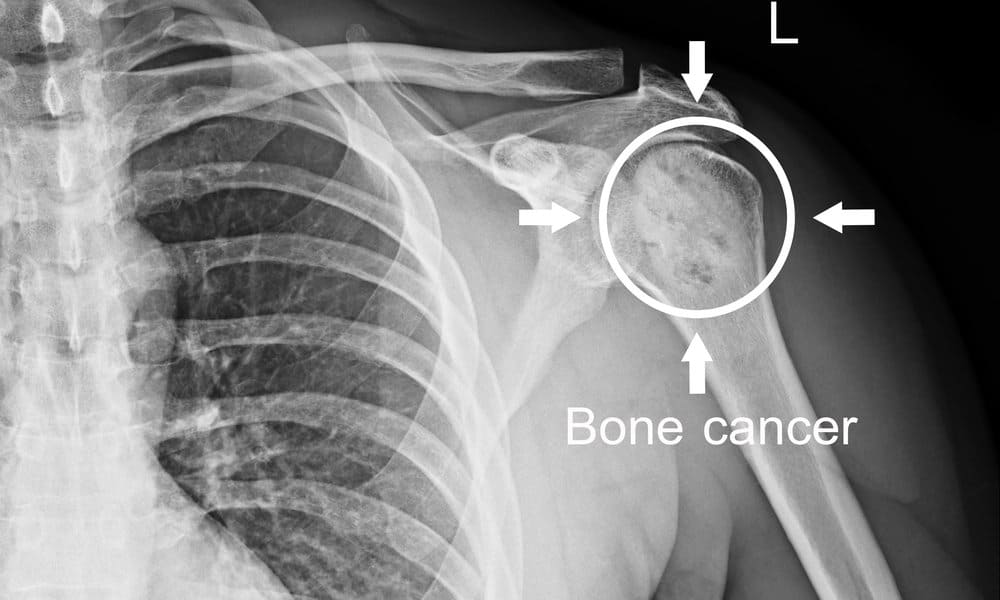

Ang kanser sa buto ay nangyayari kapag ang hindi mga pangkaraniwang cells ay lumalaki nang walang kontrol sa iyong buto. Sinisira nito ang normal na tissue ng buto. Maaari itong magsimula sa iyong buto o kumalat doon mula sa ibang bahagi ng iyong katawan na tinatawag na metastasis.

Upang masuri ang kanser sa buto, ang iyong healthcare provider ay kadalasang gagamit muna ng mga X-ray upang tingnan ang mga inisyal na larawan ng iyong mga buto. Ang magnetic resonance imaging (MRI) at CT (computed tomography) scan ay nagbibigay ng mas detalyadong mga larawan ng mga bahagi sa paligid ng mga buto at kadalasang ang resulta ng mga ito ay kailangan bago ang anumang paggamot. Magsasagawa rin ng biopsy upang kumpirmahin ang diagnosis.